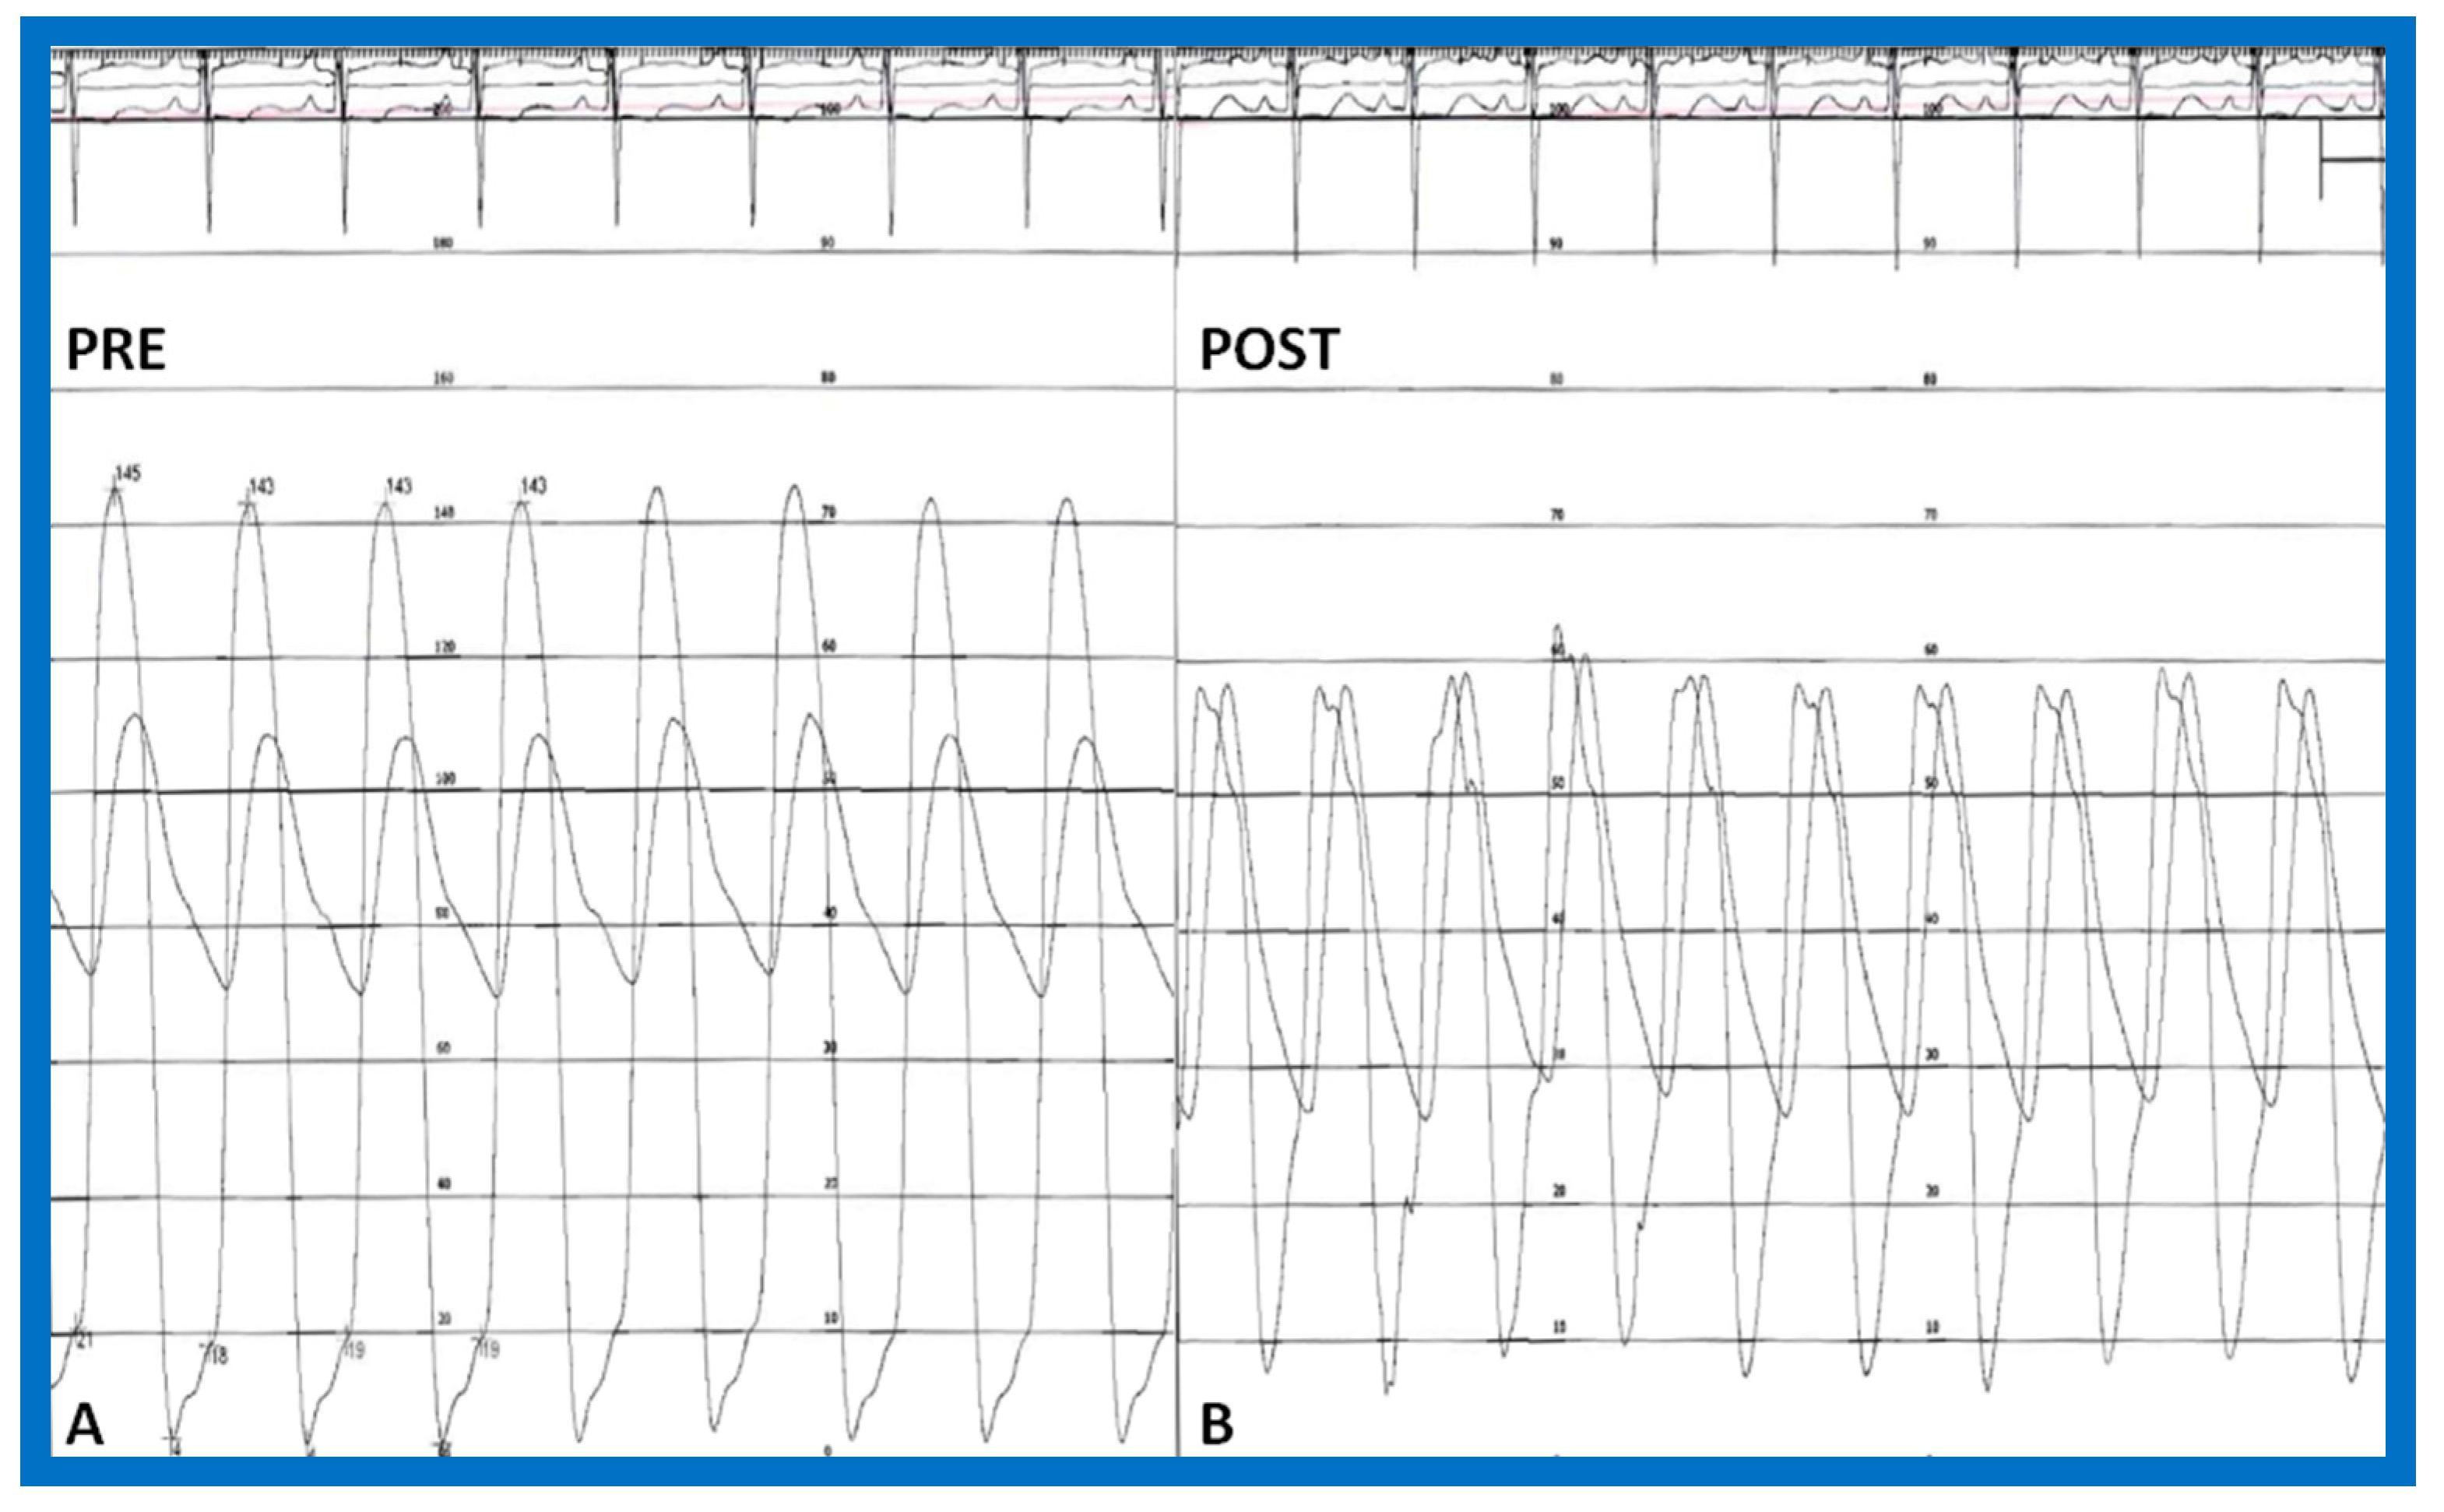

4.3. Aortic Coarctation–Native

Revisit BA in the Neonate and Young Infant